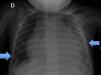

Paciente de 21 meses que presenta deterioro respiratorio durante una artrotomía de tobillo. Ingresado hacia 10 días con tratamiento antibiótico por sospecha de artritis de tobillo derecho con imágenes de edema óseo y escaso líquido articular en resonancia y ecografía articular. Previamente asintomático sin antecedentes de interés. Dada la persistencia de tumefacción articular e impotencia funcional se decide artrotomía diagnóstica. Al finalizar la intervención presenta problemas de oxigenación y ventilación junto con tonos cardiacos disminuidos. Se realiza una radiografía de tórax (fig. 1) y un ecocardiograma urgente (fig. 2, video anexo), detectándose derrame pleural y pericárdico moderados junto con lesión pericárdica de gran tamaño.